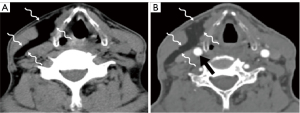

Due to its location between the vein and artery in the carotid space, schwannomas of the vagus nerve tend to separate the artery and vein, usually displacing the CCA/ICA medially and the IJV laterally (Figures 2,3) (12). Some schwannomas of the vagus nerve may displace the IJV and ICA/CCA in a posterior direction without splaying them and there is usually separation between the artery and vein (Figure 4). The cervical sympathetic chain runs in a fascial reflection posterior and slightly medial to the carotid space. Hence, schwannomas of the sympathetic chain tend to displace the IJV and CCA/ICA together, usually anteriorly and laterally (Figure 5) (5). A large schwannoma of the sympathetic chain may distort the surrounding anatomy and result in a posterior displacement of the carotid vessels without separation of the artery and vein (Figure 6) (13,14). Occasionally, a schwannoma of the cervical sympathetic chain may splay the internal and external carotid arteries at the carotid bifurcation but without encasing the arteries (Figure 7) (5). In these regards, the position of the tumor relating to the vessels in the carotid space is more important than the direction of vascular displacement. There has also been a reported case of schwannoma arising from the glossopharyngeal nerve in the carotid space causing posterior displacement of the ICA (15).